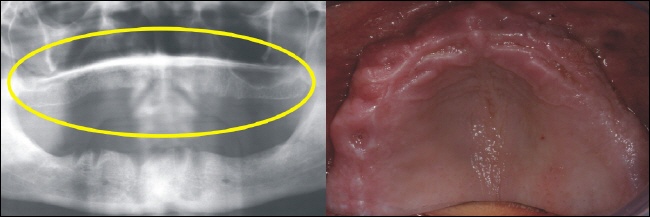

Nach der Einheilzeit werden auf die Implantate Teleskopkronen aufgesetzt, über die der Zahnersatz gesteckt wird (Oberkiefer). |

Nach der Einheilzeit werden auf die Implantate Teleskopkronen aufgesetzt über die der Zahnersatz gesteckt wird (Unterkiefer). |